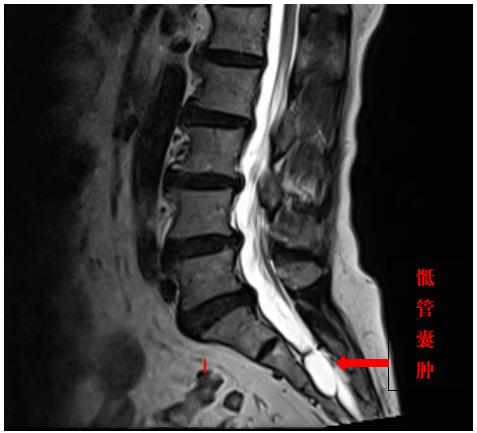

尾骨囊肿图片

尾椎骨囊肿图片

骶尾部囊肿早期图片